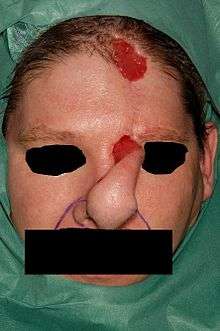

First stage

The flap is incised and elevated from distal to proximal.[1][3] Distally, the frontalis muscle and subcutaneous tissue are excised, this is done for 1.5 to 2 cm.[1][3] Then more downwards the disscection goes through the muscle and over the periosteum.[1] When reaching the brow, all of the skin borders are incised and the flap is carefully released.[1] As soon as the flap reaches the defect without tension further incision of the flap is stopped and the flap is inset into the area of the defect.[1][3][4] This is done using a single layer of fine suture.[1]

First stage

The flap is incised and elevated over the periosteum from distal to proximal.[1] The flap consists of skin, subcutaneous tissue, fat and frontalis muscle and is not thinned. When reaching the brow, all of the skin borders are incised and the flap is carefully released.[1] The full-thickness flap is then sutured into the defect without tension.